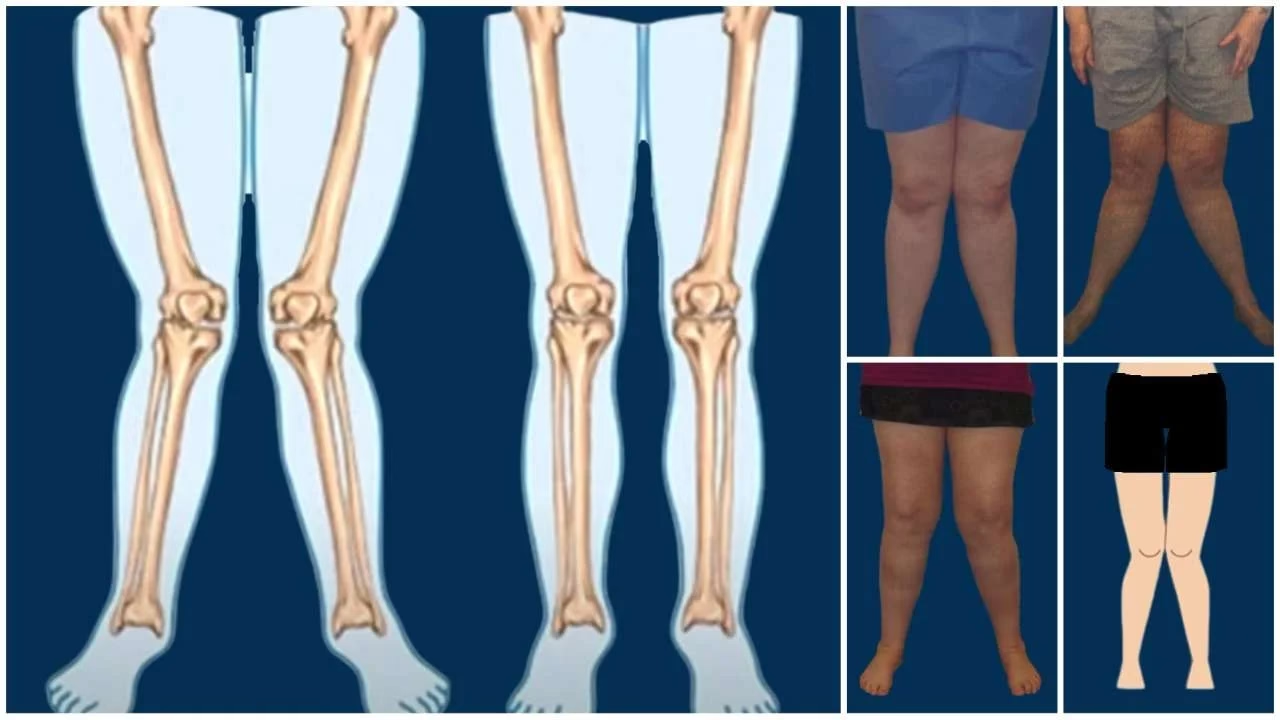

Een kniebuigreactie is een snelle en automatische reactie op iets zonder erover na te denken. Net zoals wanneer een arts op uw knie tikt en deze uitschopt zonder dat uw hersenen besluiten dit te doen, gebeurt een kniebuigreactie vanuit gewoonte of instinct, niet vanuit zorgvuldige overweging. Als iemand bijvoorbeeld plotseling een bal naar u gooit en u vangt deze zonder na te denken, dan is dat een kniebuigreactie. Het is het soort actie dat u meteen uitvoert, zonder eerst stil te staan om erover na te denken.

“Kniebuigreactie” begon als een medische term. Het beschrijft een snelle, automatische beweging van de knie, de zogenaamde patellareflex. Dit gebeurt wanneer de knie wordt aangetikt. De eerste keer dat deze reflex schriftelijk werd genoemd, was in 1877. Dat markeerde het begin als een term die door artsen werd gebruikt.

De betekenis van een kniebuigreactie is een automatische reactie, in plaats van een zorgvuldig overwogen reactie. Deze uitdrukking komt van de natuurlijke reflexen van het lichaam. Als iemand op de juiste plek op een knie tikt, zal het been naar buiten schoppen. Dit gebeurt snel, omdat het zenuwstelsel het signaal niet helemaal naar de hersenen en terug stuurt. Het is eerder een automatische reactie die van de knie naar de ruggengraat en weer terug beweegt, waardoor het snel kan gebeuren.

De “kniebuig” werd in 1877 vastgelegd in Sir Michael Foster's Text-book of Physiology:

“Het slaan van de pees onder de patella geeft aanleiding tot een plotselinge extensie van het been, bekend als de kniebuigreflex.”